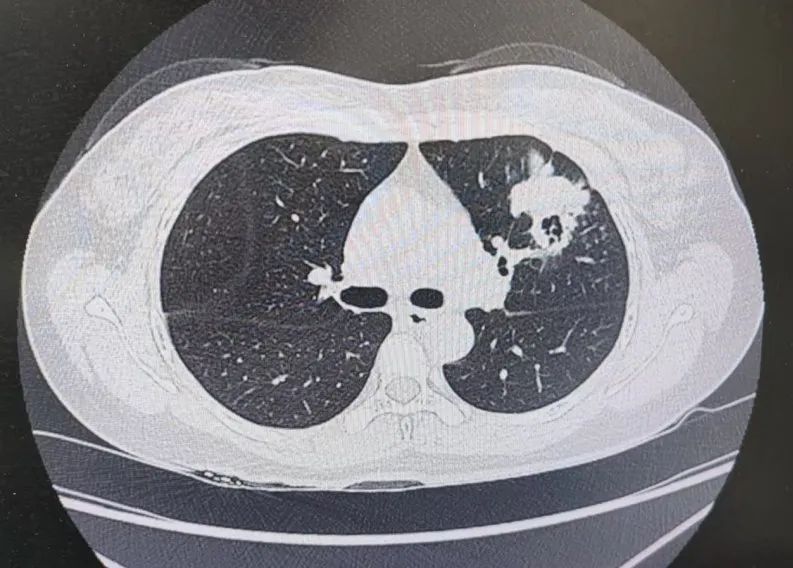

患者肺部CT影像

“一般来说,肺炎经过一周的抗感染治疗,病灶会有所吸收。但陈女士的肺部阴影纹丝不动,这种情况必须提高警惕。”宋刚主任团队立即启动了更深入的“三部精准诊断”程序:

3、CT引导下穿刺活检:病理诊断为左肺上叶腺癌。

肺炎型肺癌,因其影像学表现与普通肺炎极为相似,临床上误诊率极高。然而确诊仅是第一步。宋刚主任当天即召集肿瘤科、病理科、影像科等多学科专家会诊,为陈女士制定个体化治疗方案。